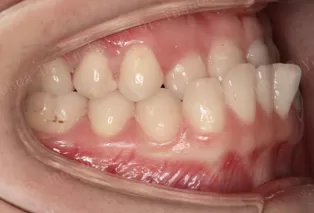

Photos intra-orales